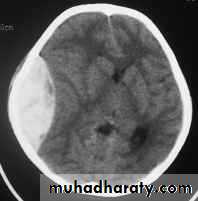

Acute Subdural Haematoma

Usually due to MORE SEVER high velocity trauma and thus associated with a poorer outcome.Source of bleeding (haematoma): include:

Most result from torn bridging veins or focal tears of a cortical artery.

Cortical lacerations or contusions.

Bleeding from tears in the dural venous sinuses.

Clinical Picture: patient will present with a picture similar to that of an extradural haematoma, but there is persistent loss of consciousness with no lucid interval.Ct scan will show a concave hyperdence collection because blood follows the subdural space over the convexity of the brain.

Acute Subdural Haematoma are rapidly evolving lesions and early evacuation via craniotomy is mandatory.